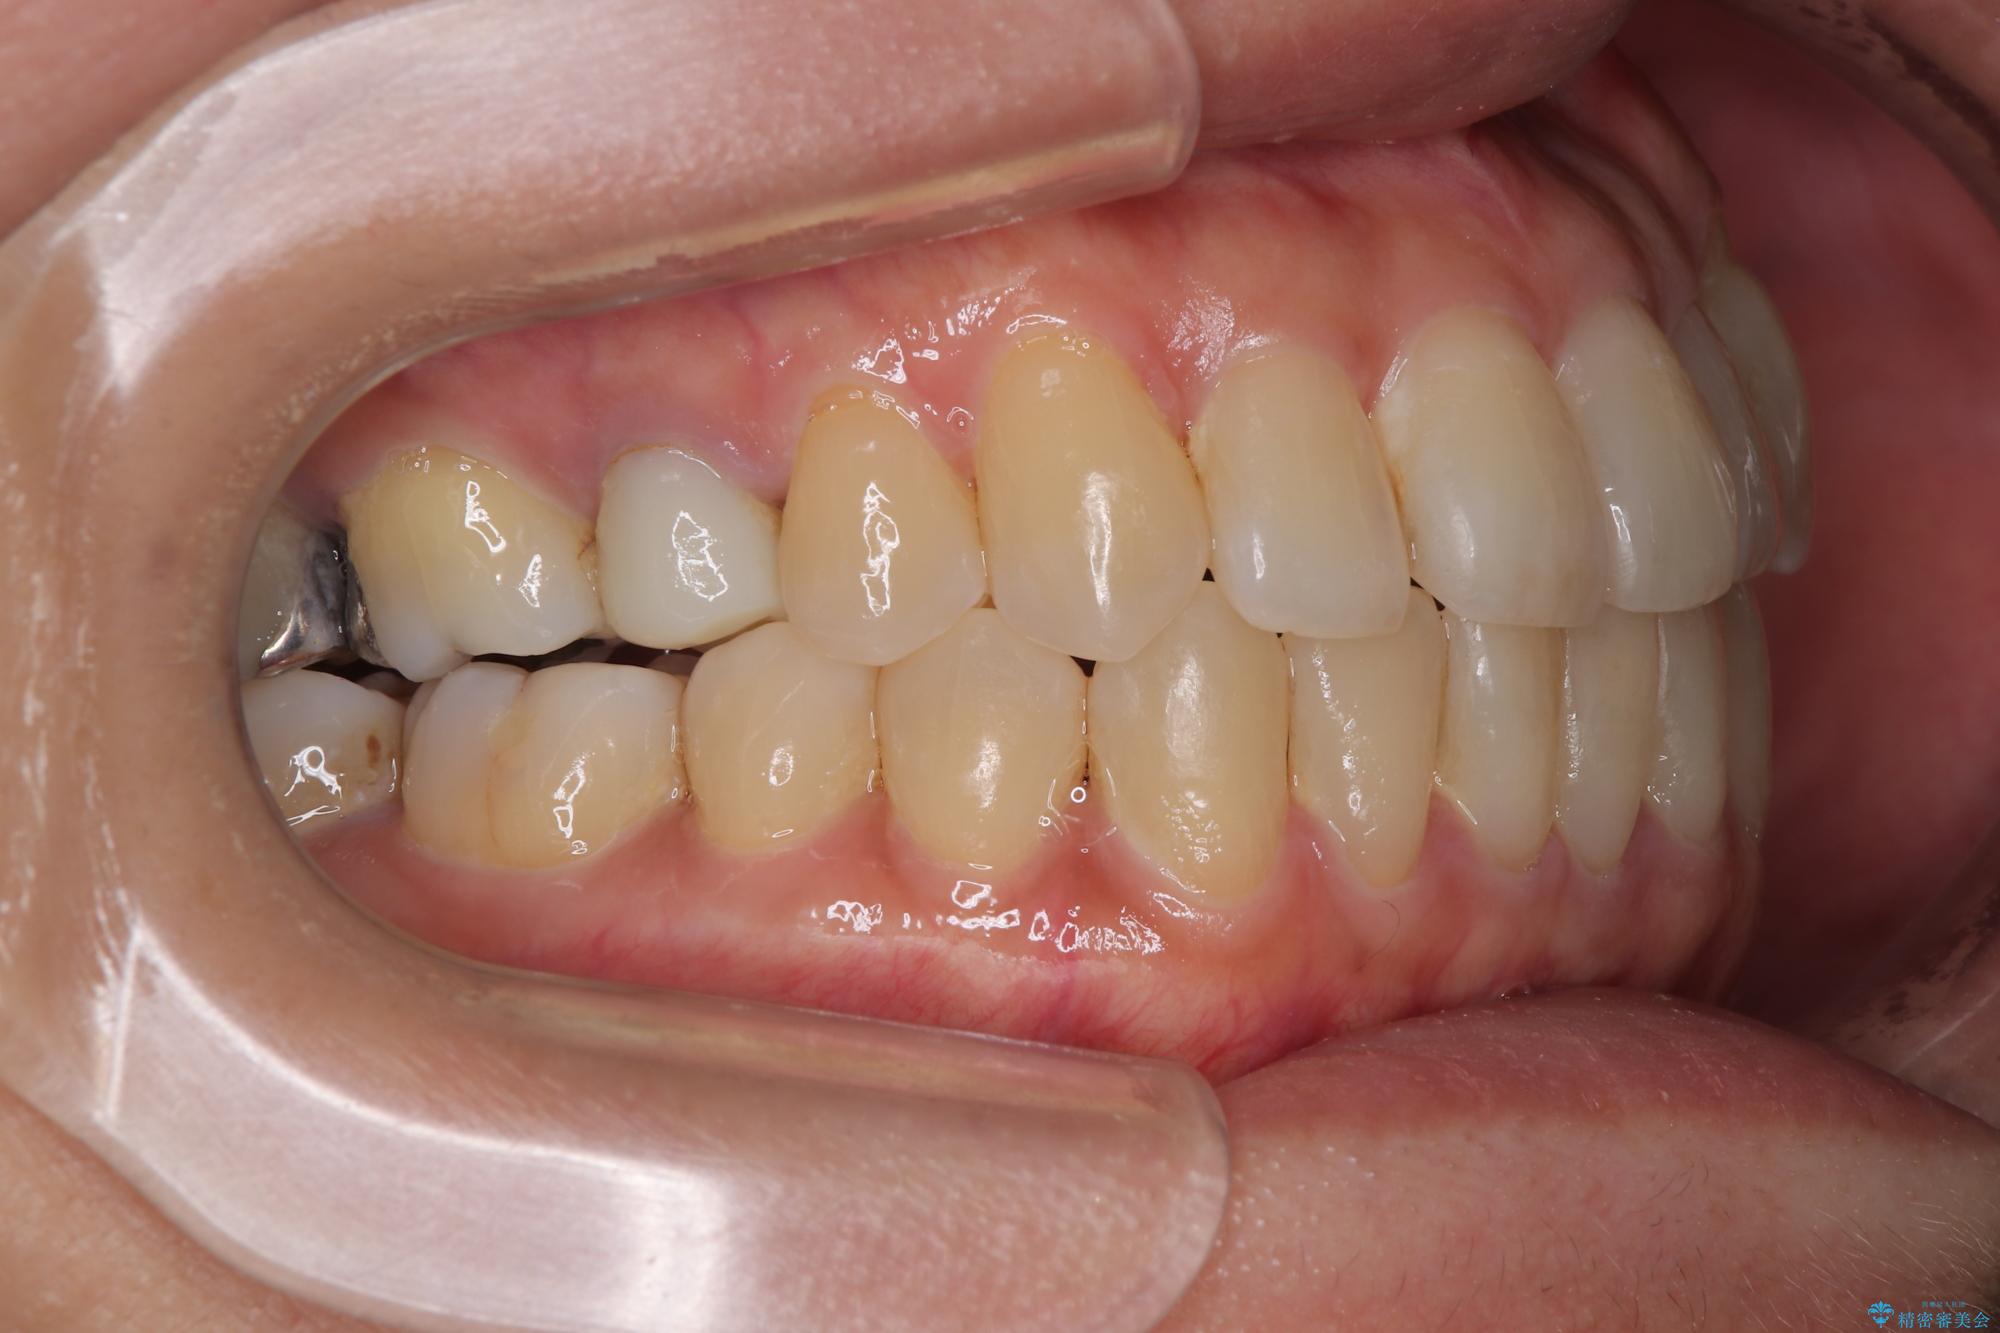

受け口と八重歯を改善 インビザライン矯正治療

- 前歯のデコボコや八重歯を治したいとのことで来院された患者様です。

受け口傾向の骨格であり、前歯はクロスバイトまたは切端咬合となっており、下顎を中心に歯列全体の後方移動を行い、IPR(歯と歯の間を削る)によってデコボコが解消するように設計し、インビザラインにより治療を行うこととしました。

受け口傾向のインビザライン矯正は比較的治療を行いやすいため、きれいに仕上げることができました。舌の突出癖が顕著であったため、改善のためのトレーニングをしっかりと行っていただきました。